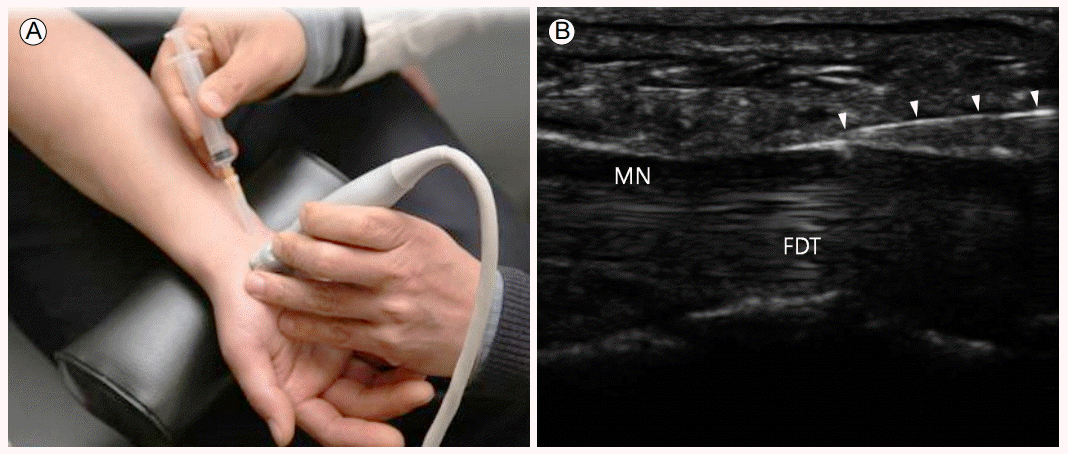

손목은 류마티스관절염이 가장 흔하게 침범하는 관절 중의 하나이다. 초음파 검사는 손목 통증과 종창의 원인이 관절내부 또는 주변의 건초염 인지를 확인하여 목표 구조물을 결정하는데 매우 유용하다. 요골수근골(radiocarpal)관절내 주사는 환자의 손목을 필로우에 올려두어 손목을 약간 굽힌 상태에서 탐촉자를 종축으로 위치한 후 lister’s tubercle 1-2 cm 원위부에서 바늘을 진입하는 방법이 있으며, 탐촉자를 손목에 횡축으로 위치한 후 요골방향에서 요골수근골 관절면에 평행하게 2nd extensor tendon compartment 아래로 통해 바늘을 진입시켜 주사하기도 한다(Fig. 6) [22].